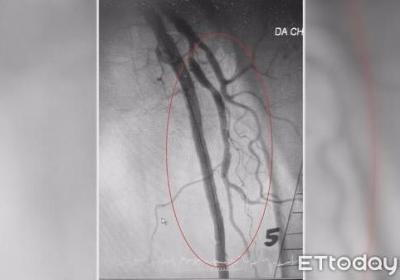

?腳也會中風(fēng)!3高患者腿部動脈易阻塞 小心潰爛、發(fā)黑要截肢,?腳也會中風(fēng)!3高患,者腿部動脈易阻塞 小,心潰爛、發(fā)黑要截肢...